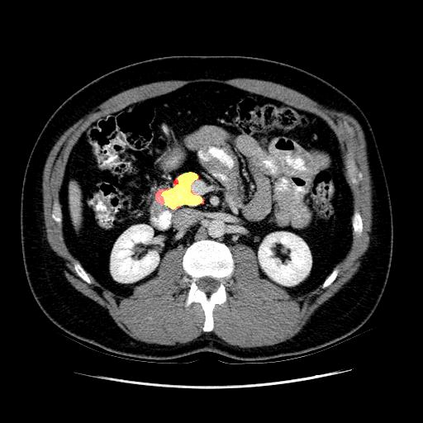

In this paper, we adopt 3D Convolutional Neural Networks to segment volumetric medical images. Although deep neural networks have been proven to be very effective on many 2D vision tasks, it is still challenging to apply them to 3D tasks due to the limited amount of annotated 3D data and limited computational resources. We propose a novel 3D-based coarse-to-fine framework to effectively and efficiently tackle these challenges. The proposed 3D-based framework outperforms the 2D counterpart to a large margin since it can leverage the rich spatial infor- mation along all three axes. We conduct experiments on two datasets which include healthy and pathological pancreases respectively, and achieve the current state-of-the-art in terms of Dice-S{\o}rensen Coefficient (DSC). On the NIH pancreas segmentation dataset, we outperform the previous best by an average of over 2%, and the worst case is improved by 7% to reach almost 70%, which indicates the reliability of our framework in clinical applications.